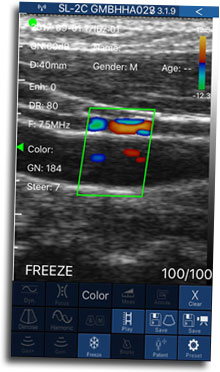

La finalidad del CIED es poner al día los conceptos básicos de la Ecografía Doppler aplicados al estudio de la enfermedad venosa crónica y su utilización en la realización de distintos tratamientos endovasculares venosos, tales como Ecoesclerosis o Escleroterapia Guiada con Ecografía (líquida y espuma o foam), Láser Endoluminal Ecoguiado y Radiofrecuencia Endoluminal Ecoguiada; así como también de las más modernas técnicas de Glue o Moca.

- Efecto Doppler, distintas funciones del equipo.

-Física del ultrasonido.

- Fisiopatología venosa evaluada a través del Ecodoppler.

- Concepto de reflujo venoso y tipos de reflujo.

- Hemodinamia venosa normal y patológica.

- Rutina paso a paso del exámen Ecodoppler color realizado en vivo.

- Práctica intensiva de procedimientos ecoguiados.